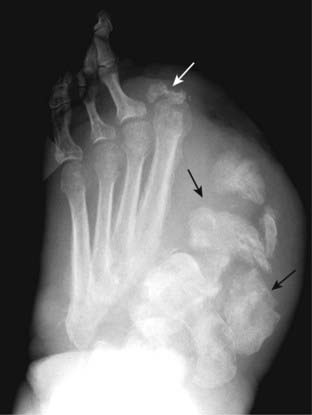

Figure 23-16 Gout.

Gout most commonly affects the metatarsal-phalangeal joint of the great toe, as in this patient. As an erosive arthritis, the hallmark of gout is the sharply marginated, juxtaarticular erosion which may have a sclerotic border (solid white arrows). The overhanging edges of gouty erosions have been called rat bites. The metatarsal-phalangeal joint space is not particularly narrowed, and there is no periarticular osteoporosis.